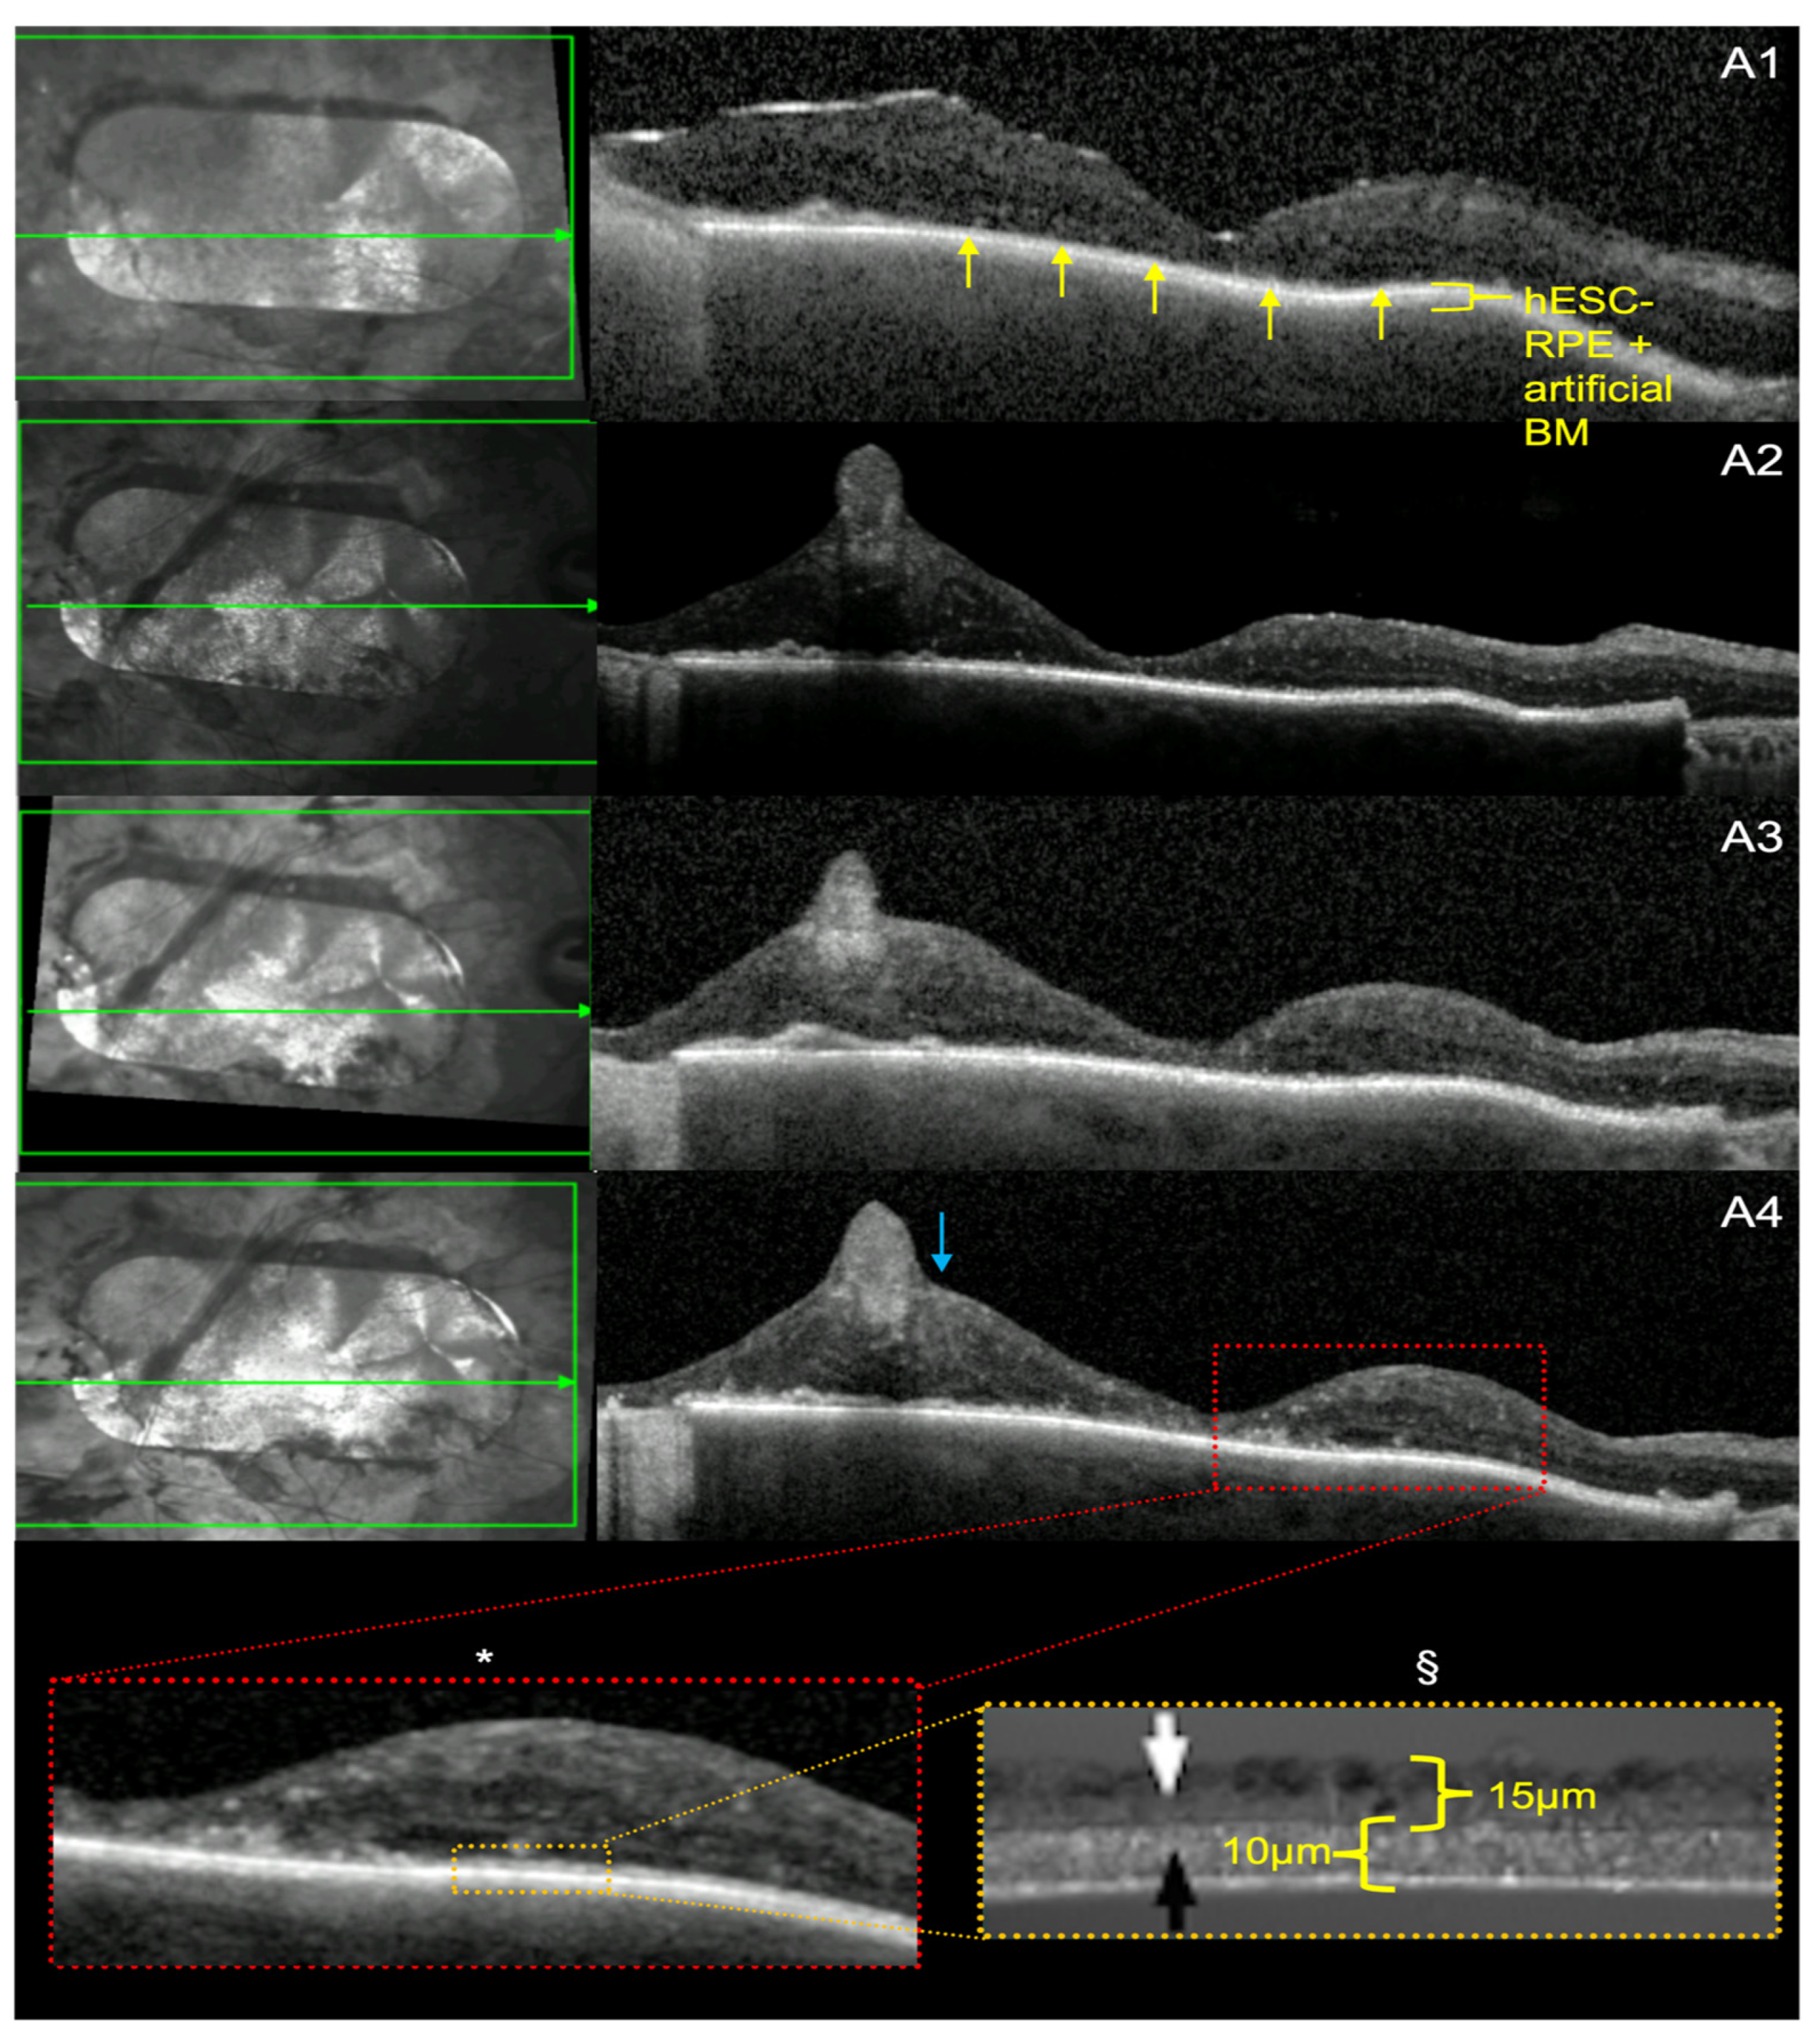

3.3. Retinal Ultrastructure

3.4. hESC-RPE and BM Thickness